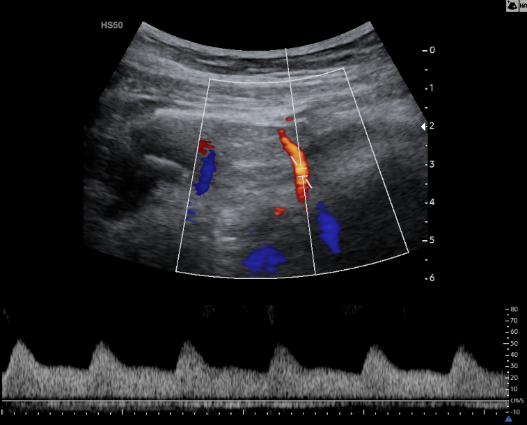

Doppler Ομφαλικής Αρτηρίας

Η Υπερηχογραφία Doppler στην Ομφαλική Αρτηρία θα μας δείξει εάν η τροφοδοσία του εμβρύου με αίμα και θρεπτικά συστατικά είναι επαρκής.

Εικόνα 03 – Φυσιολογική καμπύλη Doppler Ομφαλικής Αρτηρίας